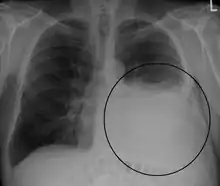

A pleural effusion appears as an area of whiteness on a standard posteroanterior chest X-ray.[12] Normally, the space between the visceral pleura and the parietal pleura cannot be seen. A pleural effusion infiltrates the space between these layers. Because the pleural effusion has a density similar to water, it can be seen on radiographs. Since the effusion has greater density than the rest of the lung, it gravitates towards the lower portions of the pleural cavity. The pleural effusion behaves according to basic fluid dynamics, conforming to the shape of pleural space, which is determined by the lung and chest wall. If the pleural space contains both air and fluid, then an air-fluid level that is horizontal will be present, instead of conforming to the lung space.[13] Chest radiographs in the lateral decubitus position (with the patient lying on the side of the pleural effusion) are more sensitive and can detect as little as 50 mL of fluid. Between 250 and 600mL of fluid must be present before upright chest X-rays can detect a pleural effusion (e.g., blunted costophrenic angles).[14]

Chest computed tomography is more accurate for diagnosis and may be obtained to better characterize the presence, size, and characteristics of a pleural effusion. Lung ultrasound, nearly as accurate as CT and more accurate than chest X-ray, is increasingly being used at the point of care to diagnose pleural effusions, with the advantage that it is a safe, dynamic, and repeatable imaging modality.[15] To increase diagnostic accuracy of detection of pleural effusion sonographically, markers such as boomerang and VIP signs can be utilized.[16]

Massive left-sided pleural effusion (whiteness) in a patient presenting with lung cancer.